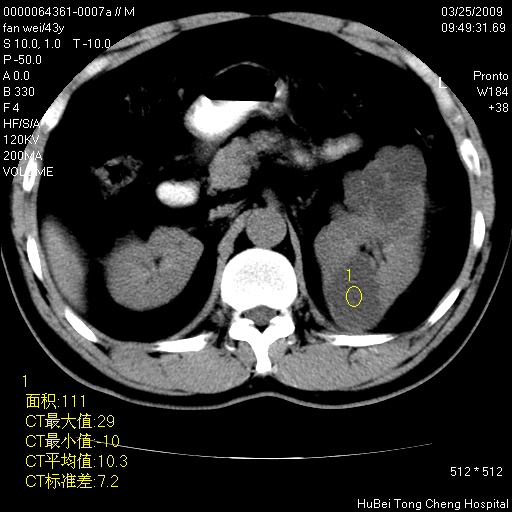

患者 男,43岁。左侧腰部不适两天。平素健康。无家族遗传病史。

腹部彩超提示:1)轻度脂肪肝。2)左肾多发囊性占位性病变;建议行进一步检查。

临床诊断:左肾多发囊性占位性病变,性质待定(多发肾囊肿?)。

双肾ct轴位平扫+增强扫描(层厚10mm,螺距1.0,重建间隔10mm),图像如下: